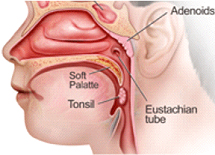

Tonsils & Adenoids